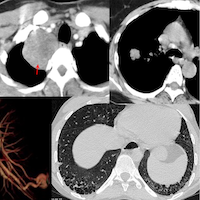

41-years old was diagnosed to have Stage III sarcoidosis last year (peribronchovascular and fissures nodules - panels C and D). He was put on treatment and the scan done recently shows significant improvement (panels A and B).